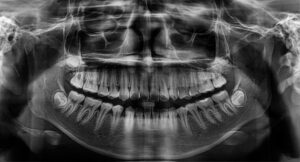

Panorex

A panorex is a very impressive piece of imaging machinery in that it is capable of identifying many issues and structures that a normal x-ray is not. Initially you will sit in a chair with your chin on a small ledge. Once positioned in the machine, it will rotate around your entire head taking a full 360 degree view of the teeth, head, sinuses and bones.

The ability to view the full structure of your head as a whole is very informative to the dentist. It will allow us to see any potential problems and make sure that everything is functioning as it should be. The panorex is capable of viewing specific types of structural problems, infections or asymmetry among many others.